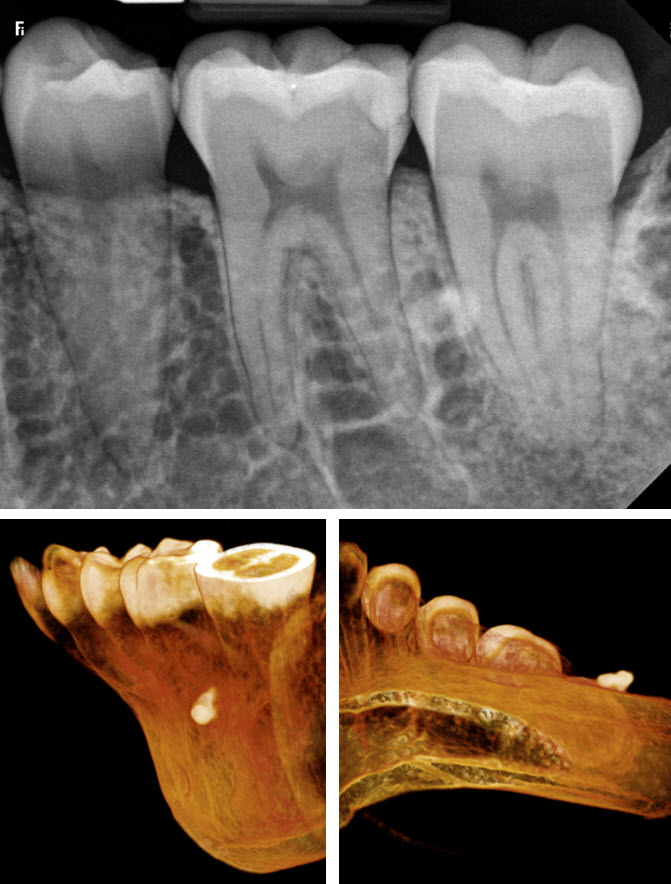

From drgstoothpix.com

Case of the Week Osteoma Cutis (2D & CBCT) Dr. G's Toothpix Osteoma Dental Treatment Osteoid osteoma of the maxilla may present as pain related to dental implants and. In some cases, dental extractions may be necessary to address an osteoma and restore oral health. Surgical treatment is frequently used in clinic, including open surgery and percutaneous ablation, the latter including radiofrequency. Treatments for osteoma include pain relief and monitoring, surgery, and radiofrequency. Treatment of. Osteoma Dental Treatment.